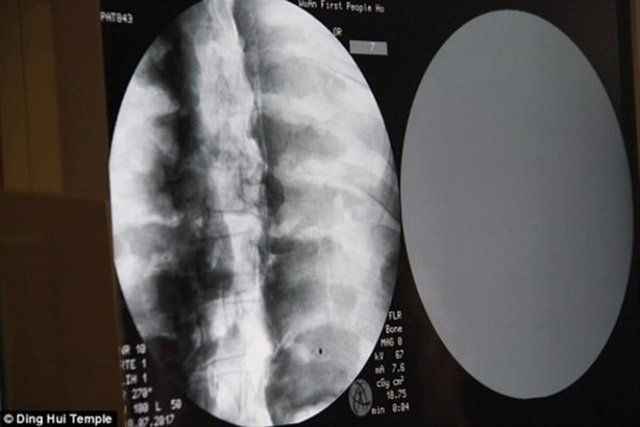

Tapınağın yönetimi, Ci Xian'ın cesedi için CT taramasını 8 Temmuz'da düzenledi. Doktorlar, Usta Ci Xian'ın, hala sağlıklı kemikleri ve bir beyni bulunduğunu söylediğinde, keşişler şok geçirdi.

Yapılan incelemede rahibin kemiklerinin hiç bozulmadığı ve beyninin zarar görmediği ortaya çıktı.

Üst çene, üst dişler, kaburga, omurga hepsi yerinde duruyor.